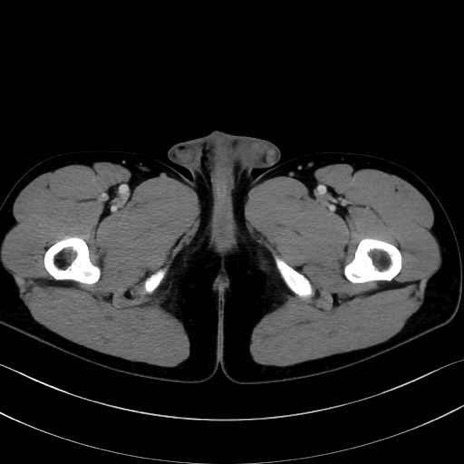

外閉鎖筋 (Obturator externus)